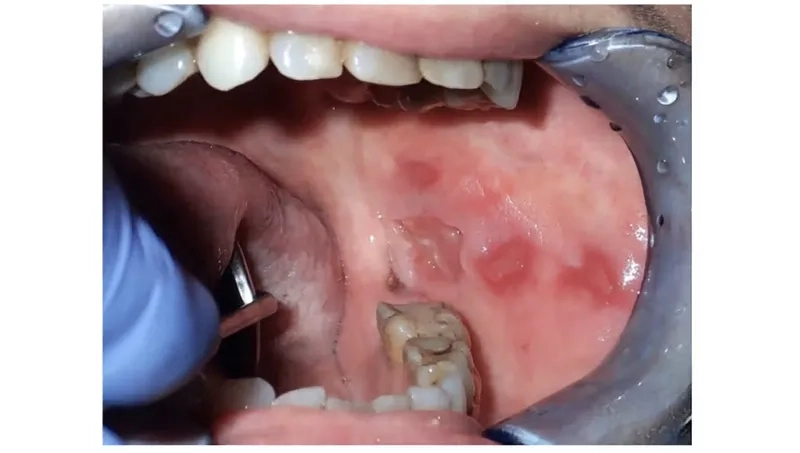

Clinical oral cancer pictures for awareness

• Be aware of red or white patches (erythroplakia or leukoplakia) on the lining of your mouth, gums, or as part of tongue cancer symptoms.

• One of the most common mouth cancer symptoms is a sore, ulcer, or irritation in the mouth or on the lip that does not heal.